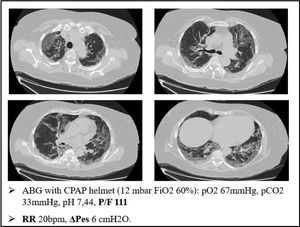

As an example of this phenomenon, we can also report one of our most plain cases of “happy hypoxemia”. Fig. 2 refers to a 67yo woman with no significant past medical history. The CT scan was taken 15 days after the onset of symptoms, and shows bilateral ground glass/crazy paving attenuation, with a visual severity score of 16/20. The patient developed severe hypoxemic respiratory failure and CPAP treatment was started. As displayed on Fig. 2, the patient was tachypneic and ABG during CPAP treatment showed severe respiratory failure. Tidal volume could not be recorded, but we did monitor the swing of esophageal pressure (ΔPes), thanks to a multifunctional nasogastric tube with a dedicated pressure transducer (NutriVent Sidam Group). The swing of esophageal pressure, during spontaneous breathing, reflects the respiratory effort.21 To reduce the confounding factor of breath to breath variability of the respiratory dynamic22, we measure esophageal pressure swing in at least two daily 3 min long recordings at rest and then calculate an average ΔPes. In this case, we measured a ΔPes of 6cmH2O: a normal respiratory effort, even if the patient had profound respiratory failure with tachypnea.

Response to PEEP/CPAPCPAP is widely used in the COVID-19 pandemic, especially in patients treated outside the ICU. Patients treated with CPAP are usually affected by type L COVID-19.33–35

CPAP has been used for decades in a variety of patients to improve arterial blood oxygenation. The main role of CPAP is keeping the alveoli open: the so called “alveolar recruitment”. In fact, CPAP can push back the transudate from the alveolar space during acute cardiogenic edema, but it can also keep the lung open when facing exudate and atelectasis due to lung infections, inflammations or classical ARDS.36,37,5

However, how can we explain the striking role of CPAP in type L SARS-CoV-2 pneumonia, since our biopsies showed no sign of alveolar edema, hyaline membranes or atelectasis?

Again, we can explain this phenomenon as a matter of V/Q ratio. The increased alveolar pressure given by CPAP might help by inflating the alveoli, thereby squeezing the capillaries next to them, reducing the V/Q ratio inequality (Fig. 5)

For example, Fig. 6 refers to a 76yo male, former smoker, with a past medical history of arterial blood hypertension and moderate chronic kidney disease. The CT scan was obtained after 7 days from the onset of symptoms and shows bilateral ground glass attenuation and crazy paving typical of the early phases of SARS-CoV-2 pneumonia. Visual severity score was 14/20. The high flow CPAP strongly ameliorated the arterial blood oxygenation after few minutes. The results of our biopsy suggest that such a quick improvement could be explained with a redistribution of lung perfusion, along with alveolar hyperinflation. A new balance in V/Q was reached.